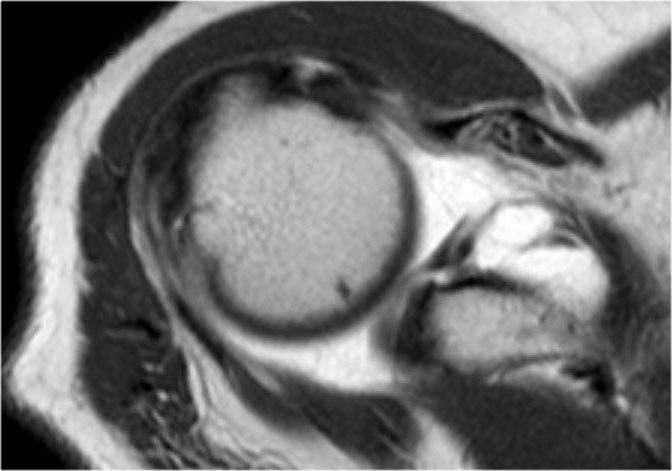

Tổn thương Perthes

Tổn thương Perthes là avulsion sụn viền-dây chằng tương tự Bankart, nhưng với màng xương bị bóc tách về phía trong mà vẫn còn nguyên vẹn.

Trên hình ảnh khớp vai ở tư thế trung gian, sụn viền bị rách có thể được giữ ở vị trí giải phẫu bình thường bởi màng xương bả vai còn nguyên vẹn, từ đó ngăn thuốc tương phản từ thấm vào đường rách.

Điều này có nghĩa là MRI khớp cản từ ở tư thế trung gian có thể không phát hiện được đường rách sụn viền.

Tuy nhiên, ở tư thế ABER, dây chằng ổ chảo-cánh tay dưới bó trước bị căng tạo lực kéo lên sụn viền trước-dưới, giúp tăng khả năng phát hiện đường rách.

Mũi tên chỉ vào màng xương còn nguyên vẹn.

Các hình ảnh ở tư thế ABER cho thấy sụn viền trước bị bong tách.

Hình bên phải được xoay 90° ngược chiều kim đồng hồ.

Đôi khi điều này giúp hiểu rõ hơn về giải phẫu.